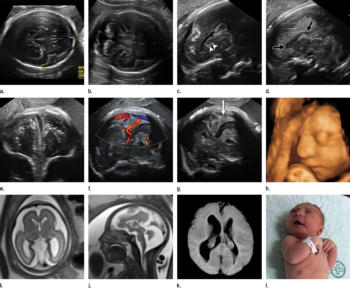

Figure 3. Images obtained in the case of a 34-year-old woman with confirmed Zika virus infection, initially seen for a rash at 8 weeks of gestation. Fetal head cir¬cumference was in the normal range at 12 and 16 weeks (5.8 cm and 11.9 cm, respectively) but then decreased to the 10th percentile at 22 weeks and was below the 3rd percentile in subsequent imaging examinations. (a–h) US images were obtained at 30 weeks. Head circumference on the axial image (a) measured 24 cm (˂2.3 percentile, corresponding to a gestational age of 26 weeks 3 days). Note the open sylvian fissures and relatively smooth cortex, which are abnormal findings at this gestational age. Oblique axial image (b) shows cerebellar calcifications (seen as the echogenic outer contour of the cerebellar hemispheres) and inferior vermian hypoplasia with associated enlarged cisterna magna. A sagittal transvaginal image (c) shows calcifications in the basal ganglia (arrowheads) and more bulky calcifi¬cation at the gray matter–white matter junction. Another sagittal transvaginal image (d) shows a relatively small corpus callosum (arrows). A coronal image (e) shows cortical and subcortical white matter calcifications in a linear pattern. The gyral pattern is abnormal, which is suggestive of polymicrogyria. A sagittal Color Doppler image (f) shows a stretched appearance of vessels coursing into the posterior fossa. An oblique axial grayscale transvaginal image in the posterior fossa (g) shows heterogeneous material in the confluence of sinuses due to blood clot (arrow). A three-dimensional US image of the face (h) shows a sloping forehead, compatible with frontal lobe hypoplasia. (i) Axial and (j) sagittal fetal MR images obtained at 29 weeks show atrophic frontal lobes, wide sylvian fissures, enlarged posterior fossa, abnormal gyral pattern, prominent cerebrospinal fluid spaces, and inferior vermian hypoplasia. On (i), note the diffuse hypointense and undersulcated cortex, which is suggestive of mineralization and polymicrogyria. The hypoplastic corpus callosum can be seen on the sagittal view (j), as well as the inferior vermian hypoplasia, en¬larged cisterna magna, and heterogeneous signal intensity in the confluence of sinuses. There is a subjectively thin spinal cord. (k) Postnatal axial MR image obtained at 81 days shows small frontal lobes and cortical thickening. The choroid plexi are enlarged. (l) Photograph of the neonate after birth.